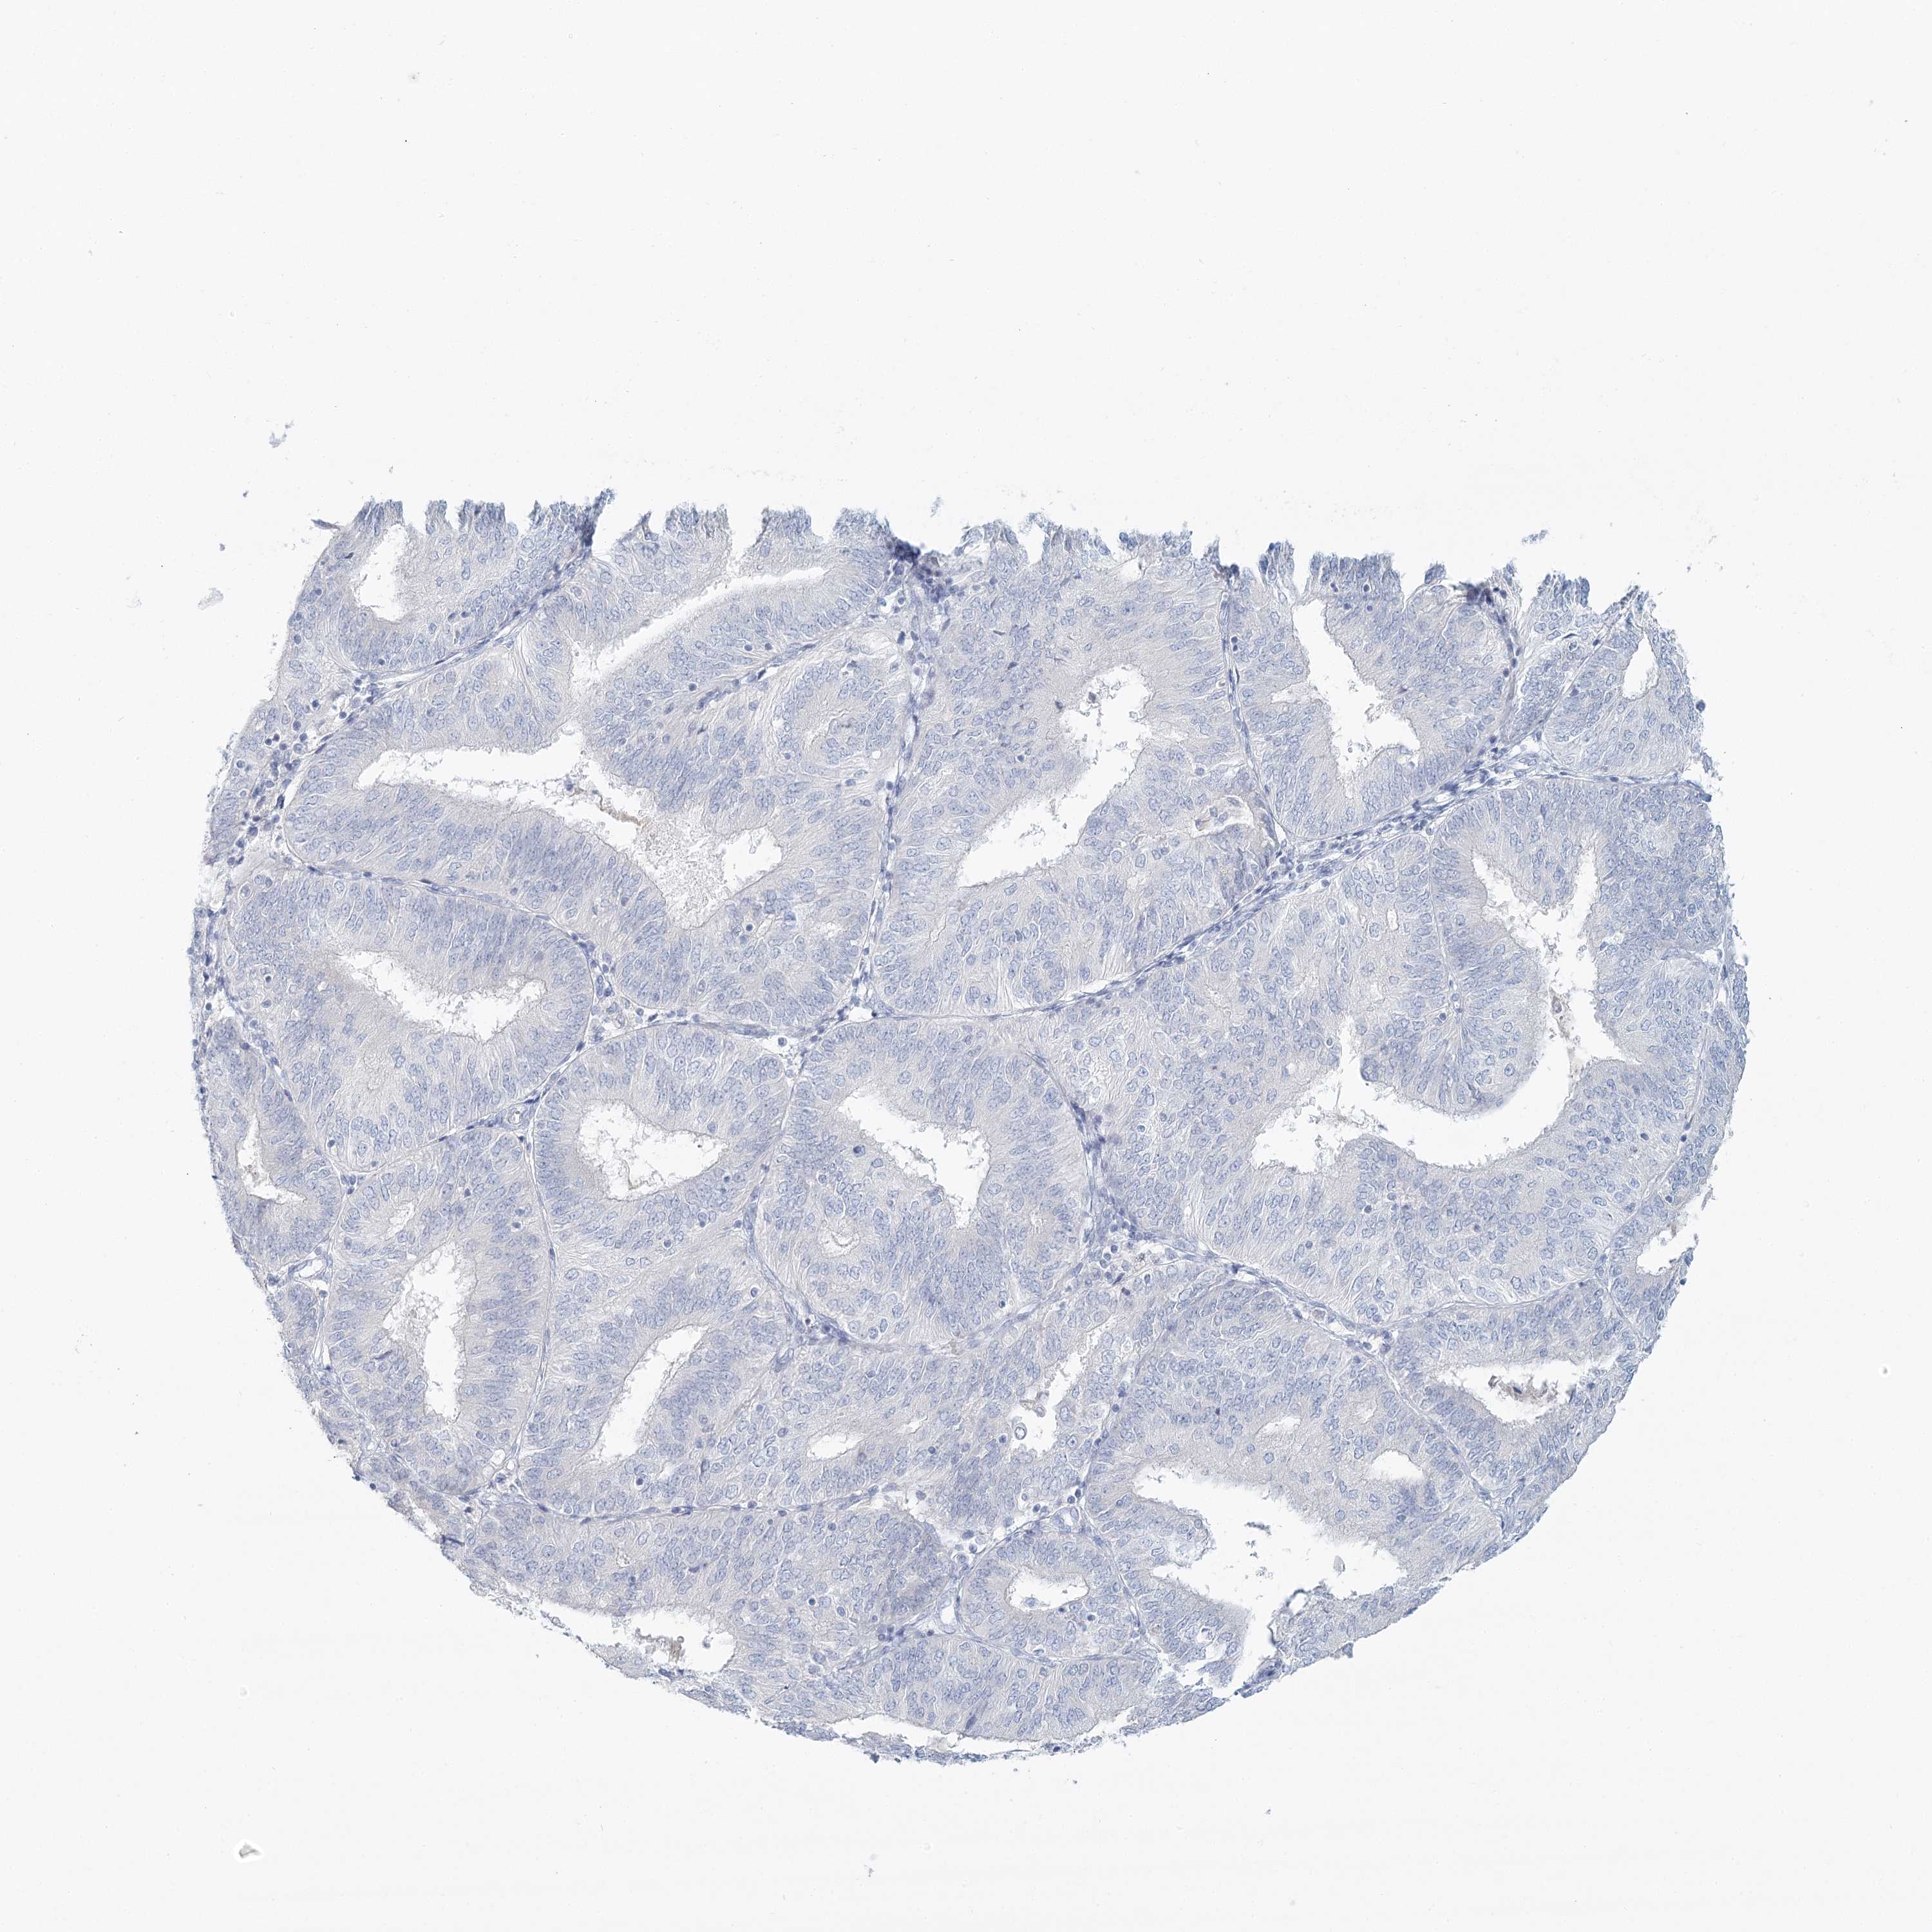

ENDOMETRIAL CANCER - Protein expressioni

A mouse-over function shows sample information and annotation data. Click on an image to view it in a full screen mode. Samples can be filtered based on level of antibody staining by selecting one or several of the following categories: high, medium, low and not detected. The assay and annotation is described here.

Note that samples used for immunohistochemistry by the Human Protein Atlas do not correspond to samples in the TCGA dataset.

Antibody stainingi

Antibody staining in the annotated cell types in the current human tissue is reported as not detected, low, medium, or high, based on conventional immunohistochemistry profiling in selected tissues. This score is based on the combination of the staining intensity and fraction of stained cells.

Each image is clickable and will lead to virtual microscopy that enables deeper exploration of all samples and also displays staining intensity scores, fraction scores and subcellular localization as well as patient and tissue information for each sample.

Antibody HPA036441

Antibody HPA036442

Staining

High

Medium

Low

Not detected

Intensity

Strong

Moderate

Weak

Negative

Quantity

>75%

75%-25%

<25%

None

Location

Nuclear

Cytoplasmic/membranous

Cytoplasmic/membranous,nuclear

Adenocarcinoma, NOS

Adenoma, NOS